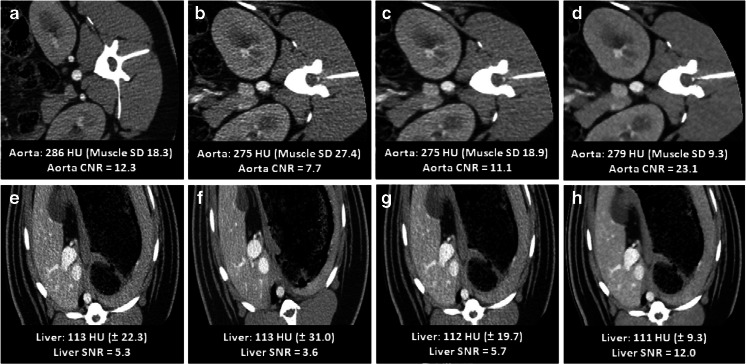

For subjective image quality, three 80 kVp, 170 mg I/mL study protocol scans with median CTDIvol of 7.1 mGy were considered (Table 4, Fig. 5). Compared to the reference, no difference in subjective image quality parameters was observed with the 80 kVp, 170 mg I/mL study protocol for ASiR reconstruction (Table 4, Fig. 5). All scans were of at least acceptable quality. With Veo reconstruction, overall quality was rated better than reference (3.3 compared to 2.7) and in particular image noise was perceived to be less present (4.3 compared to 2.5).

Fig. 5.

120 kVp, 320 mg I/mL reference protocol compared to 80 kVp, 170 mg I/mL study protocol. a Arterial and e venous phase images obtained with the reference protocol of 120 kVp, 320 mg I/mL, CTDIvol = 7.2 mGy and FBP reconstruction. b–d Arterial and f, g venous phase images obtained with a study protocol of 80 kVp, 170 mg I/mL, CTDIvol = 5.9 mGy and FBP (b, f) reconstruction, ASiR (c, g) reconstruction and Veo (d, h) reconstruction. Recorded CT values, noise, CNR and SNR are shown on each image. Note the reduced quality of the 80-kVp FBP images (b, f), which is restored by ASiR (c, g) and Veo (d, h) reconstruction